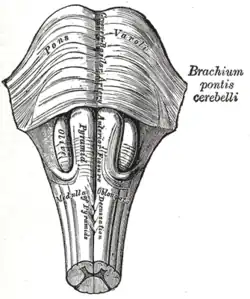

Puntea lui Varolio (latină: pons Varolii), numită și protuberanța inelară, reprezintă o formațiune nervoasă care anatomic se află plasată în completarea bulbului rahidian, aici închizându-se numeroase circuite reflexe cu însemnătate dominant defensive. Ca formă, puntea are un aspect cuboid cu înălțimea de 26 mm, lățimea de 35 mm și grosimea de 25 mm.[1] Formațiunea poartă numele anatomistului italian Costanzo Varolio (1543–1575).[2]

Puntea are aspect cuboid și se prezintă sub forma unei benzi de substanță albă, formată din fascicule de fibre transversale pe extremitatea superioară a bulbului. Are o față anterioară, una posterioară, două fețe laterale și două margini (una inferioară și una superioară). Fața anterioară este străbătută pe linia mediană de un șanț longitudinal (șanțul bazilar), în interiorul căruia se situează trunchiul arterial bazilar.[1] Pe marginile șanțului se reliefează două umflături numite piramide pontine, prelungire la acest nivel a piramidelor bulbare. Lateral de piramidele pontine se află emergența nervului trigemen. Fețele laterale se continuă cu pedunculii cerebeloși mijlocii. Fața posterioară acoperită de cerebel are o formă triunghiulară și constituie jumătatea superioară a podișului ventriculului al patrulea.[1]

În grosimea punții se disting două segmente: unul anterior, numit picior și altul posterior, numit calotă. Cele două segmente sunt despărțite de corpul trapezoid. Pe linia mediană se observă o încrucișare de fibre, formațiune ce poartă numele de rafeu. Acesta împarte puntea în două jumătăți simetrice.